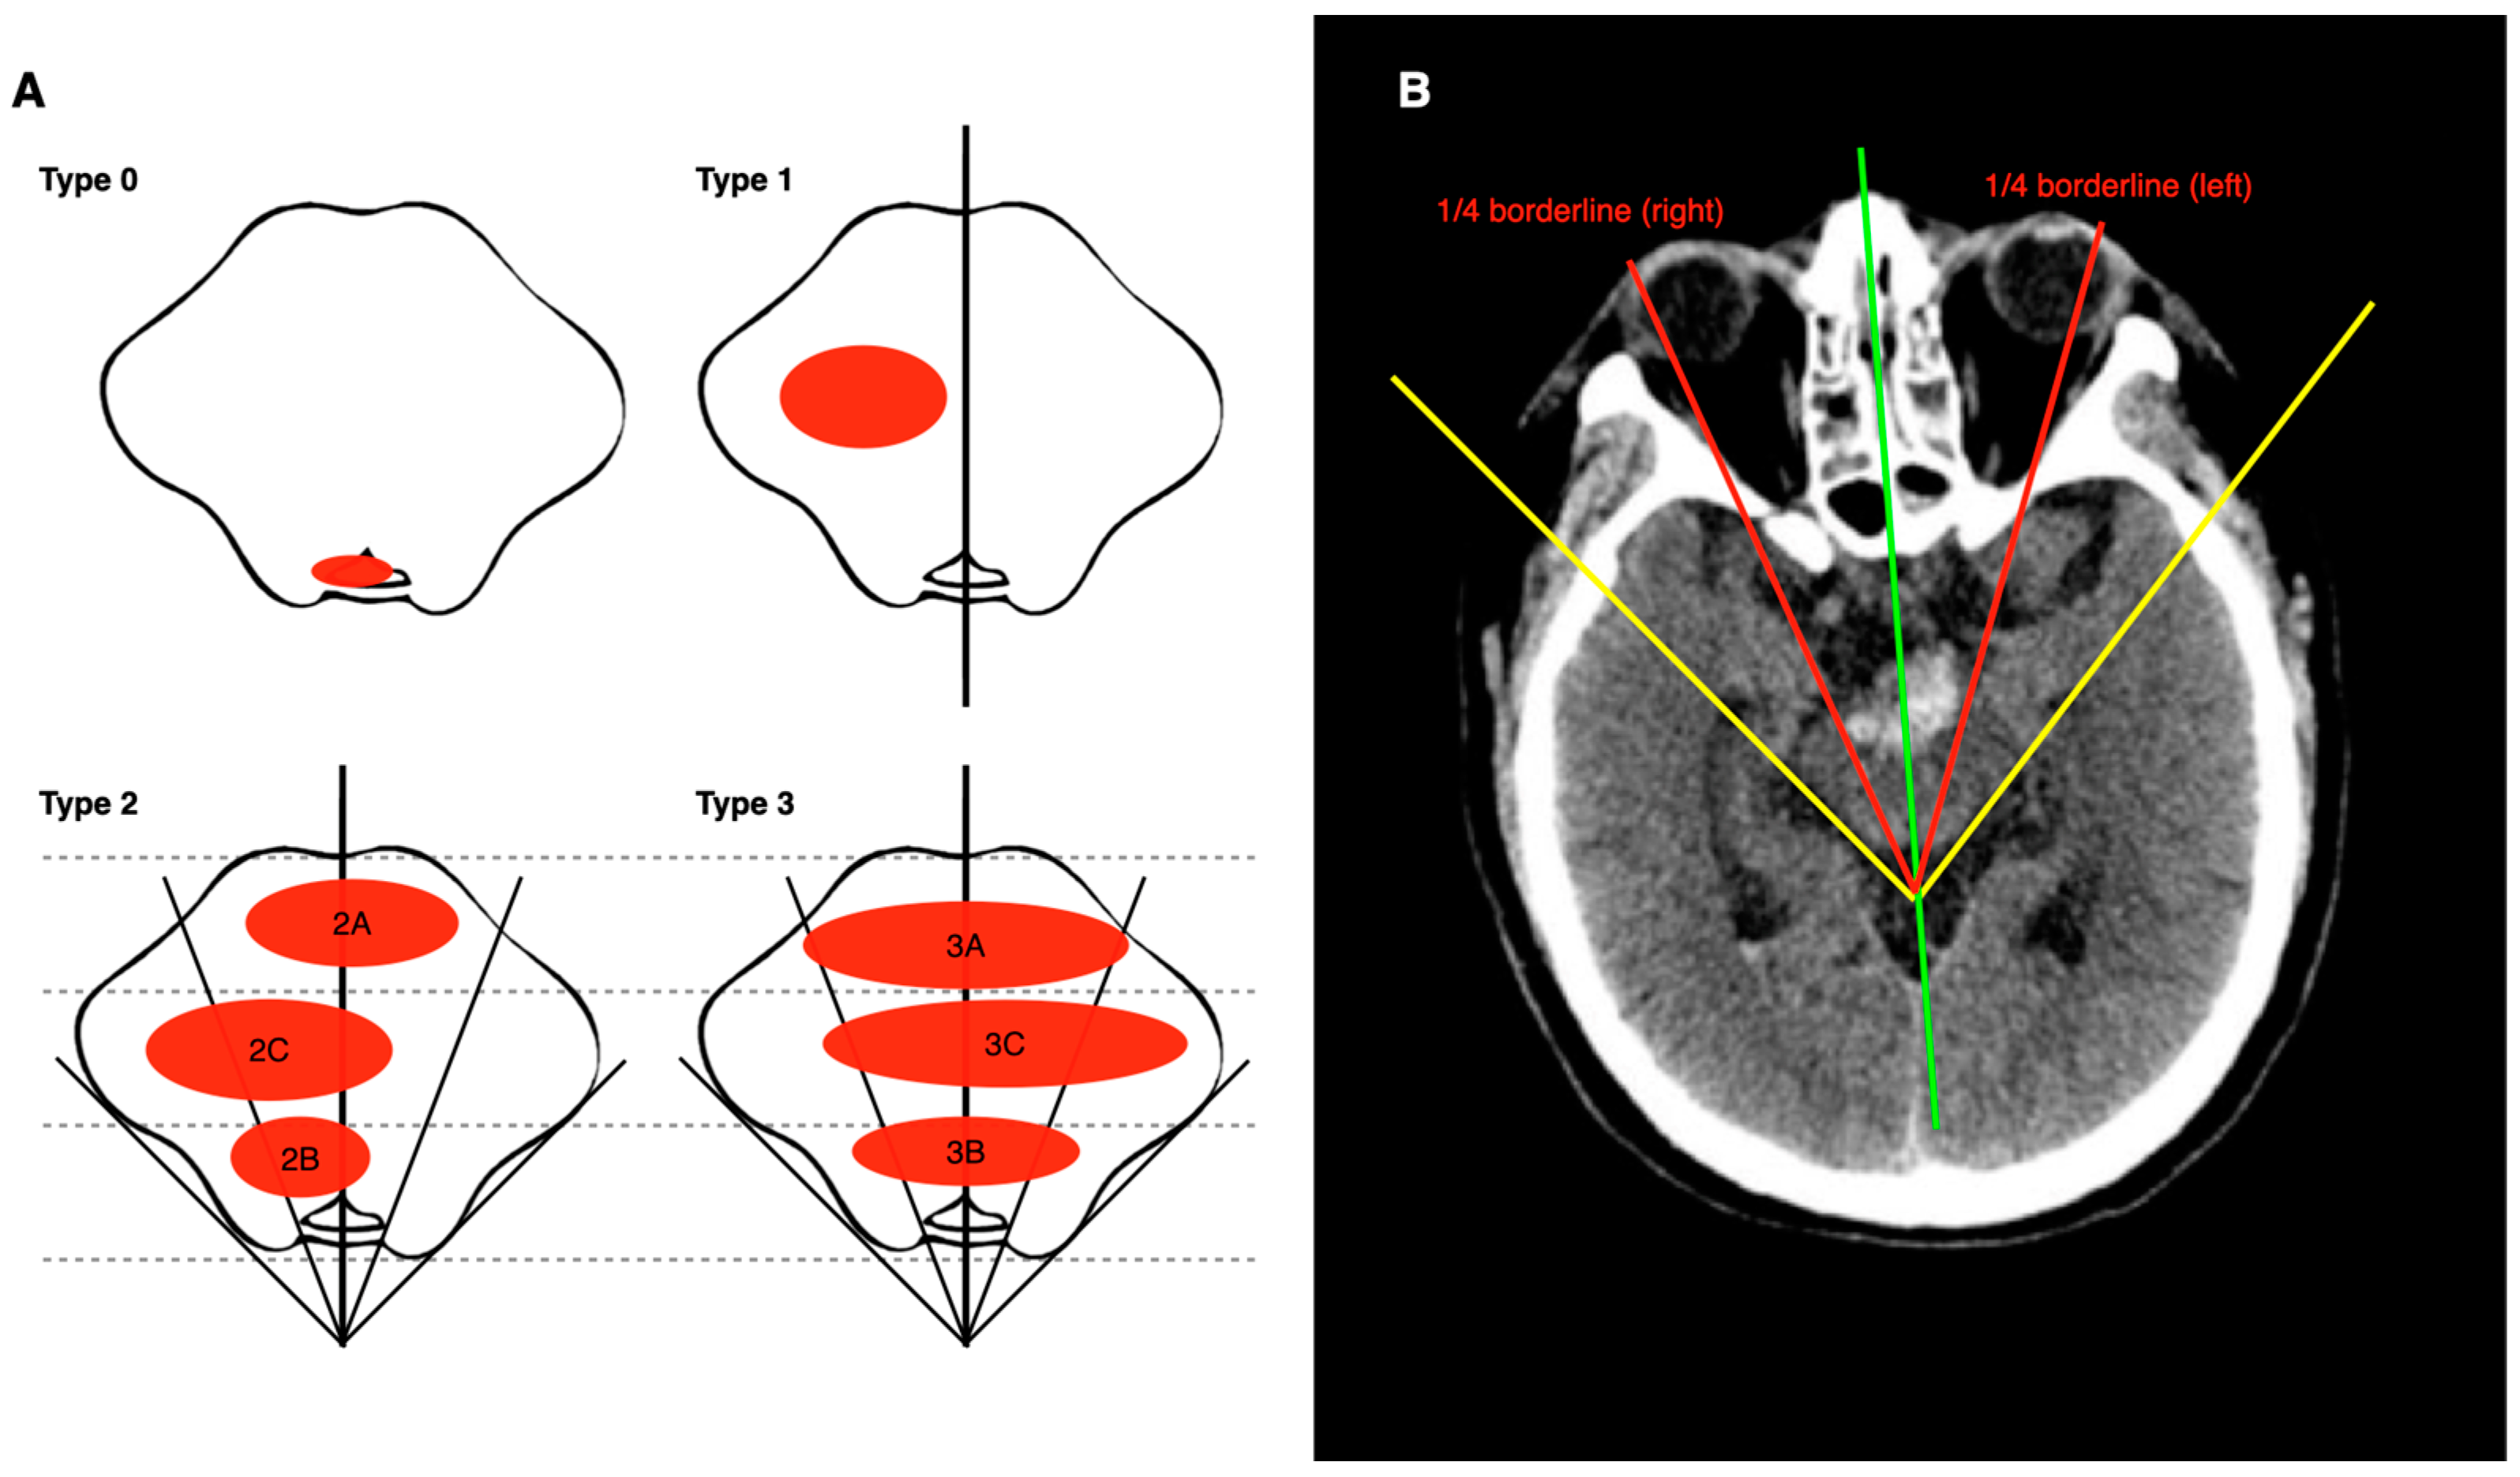

- Chung, C.S.; Park, C.H. Primary pontine hemorrhage: A new CT classification. Neurology 1992, 42, 830–834. [Google Scholar] [CrossRef] [PubMed]